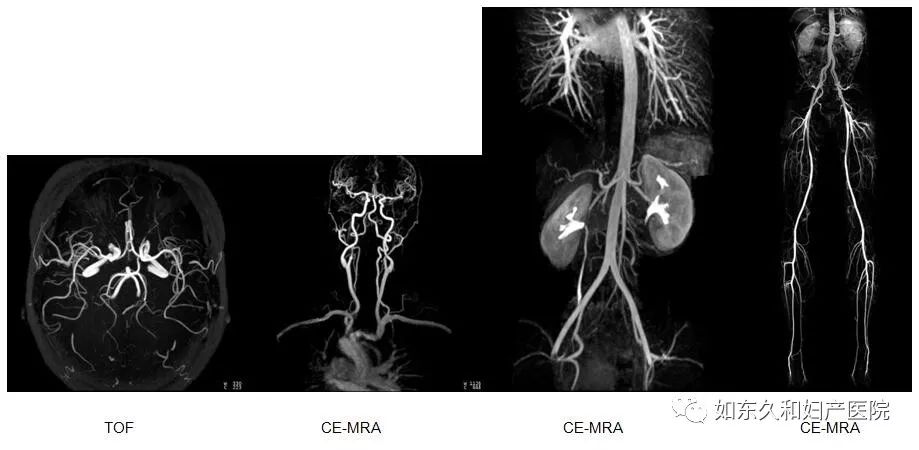

血管成像

血管成像包括多种血管成像序列进行动、静脉成像,包括造影剂增强磁共振血管成像技术及无造影剂磁共振血管成像技术,以利于观察动脉和静脉,明确血管性疾病。结合西门子独有Tim全景成像技术,可以进行大范围体部血管成像以及下肢血管成像。